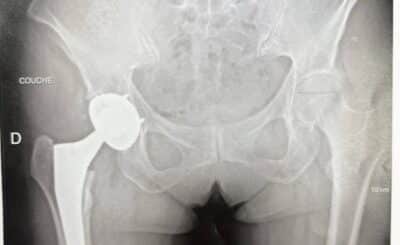

L’intervention la plus fréquente en chirurgie de la hanche est l’implantation de prothèse de hanche primaire sur coxarth...